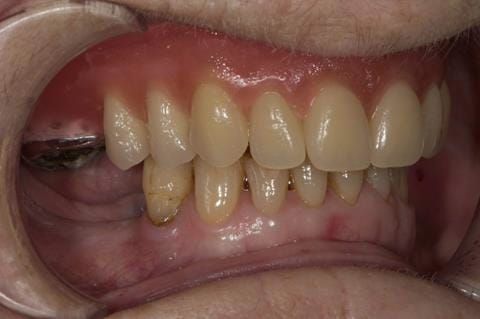

- UR7 - occlusal amalgam. 10- 20% alveolar bone loss. Healthy periodontium with reduced attachment level. No mobility.

Following consultation and second discussion appointment the patient chose to have option 2 namely, a window denture - maxillary cobalt chromium based partial denture. The clinical situation and treatment process is shown in detail below with photographs. The patient was successfully rehabilitated with this and her quality of life considerably improved. The clinical work was provided by Finlay and the technical work by Rowan.